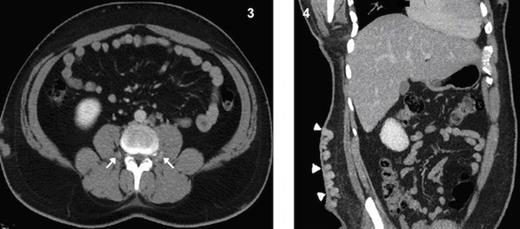

Axial CT image shows collateralization of paraspinal veins (arrows) Fig 4. Coronal MPR CT image shows massive varices of superficial collateral veins at the abdominal wall.